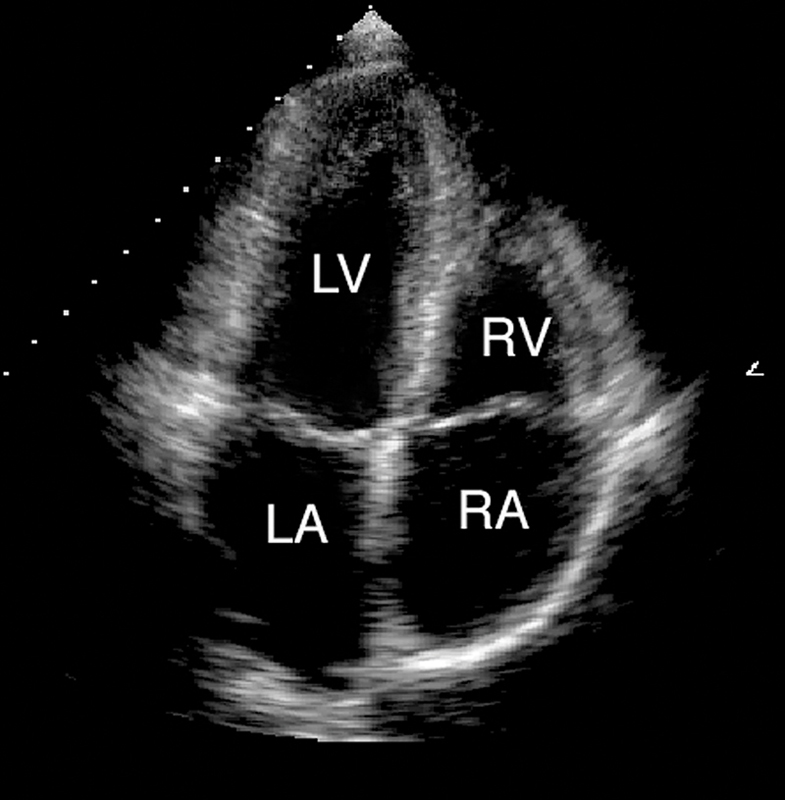

فحوصات تشخيصية لبعض امراض القلب والشرايين التاجية